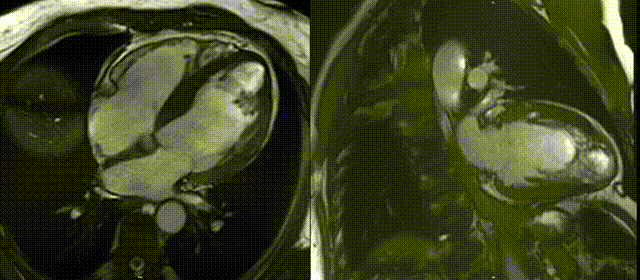

通过首过灌注(FPP)和长反转时间(TI)早期钆增强(EGE)及 LGE 序列确定排除了血栓(图 D,视频 4)。

图D 长反转时间(600 ms)早期钆增强序列显示无血栓存在

FPP是一种在钆对比剂(GBCA)团注后快速对心脏进行成像的技术。通过快速显示左心室腔的对比剂填充(高信号),以及几秒钟后正常心肌的灌注,可区分低灌注结构(如缺血心肌、瘢痕或血栓)与正常心肌或血管结构(如恶性肿物、血管瘤等)。血栓作为无血管结构,不摄取对比剂,显示为低信号,而正常心肌灌注显示为高信号。